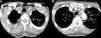

Caso clínicoMujer de 65 años, con antecedentes de asma bronquial, con bronquiectasias, APs con afectación mixta erosiva HLA-B27 negativo, tratada con metotrexato y leflunomida desde 2011 hasta 2013 por remisión. Acude por fiebre y astenia de 2 meses de evolución. No refería cefalea, alteraciones visuales, dolor toraco-abdominal ni en extremidades. En la exploración únicamente presentaba diferencia de presión arterial de 20mmHg y unos pulsos disminuidos en las extremidades izquierdas. Las arterias temporales no eran dolorosas a la palpación con pulso conservado y simétrico. En analítica se objetivó Hb de 9,9g/dl (12,0-15,0), velocidad de sedimentación globular 102mm/h (0-20), proteína C reactiva 140,90mg/l (< 5mg/l) e hierro 11 μg/dl (35,0-145,0). El resto de los parámetros fueron normales (TSH, CPK, Mantoux, marcadores tumorales, proteinograma, serologías, inmunología, sedimento orina y cultivos). La radiografía de tórax, el ecocardiograma, la gastroscopia con biopsia duodenal y la colonoscopia fueron normales. En la tomografía axial computarizada (TAC) toraco-abdominal se observaron bronquiectasias estables y un engrosamiento de la pared arterial de la aorta abdominal, indicativo de aortitis. Se amplió estudio con angio-TAC (fig. 1), que objetivó engrosamiento inflamatorio concéntrico de troncos supraórticos y cayado aórtico. Se realizó biopsia de la arteria temporal con confirmación histológica de ACG. Se inició tratamiento con corticoides a dosis de 2mg/kg/día en pauta descendente y metotrexato 15mg/semanal, quedando asintomática.

Angio-TAC: se confirma la presencia de un engrosamiento inflamatorio concéntrico/vasculitis de todos los troncos supraórticos (A) y del cayado aórtico (B) (flechas). La mayor afectación parece de la arteria subclavia izquierda, sin que se demuestren estenosis significativas a ningún nivel. En territorio carotídeo solo parece afectarse las carótidas comunes, sin extensión a ACI.